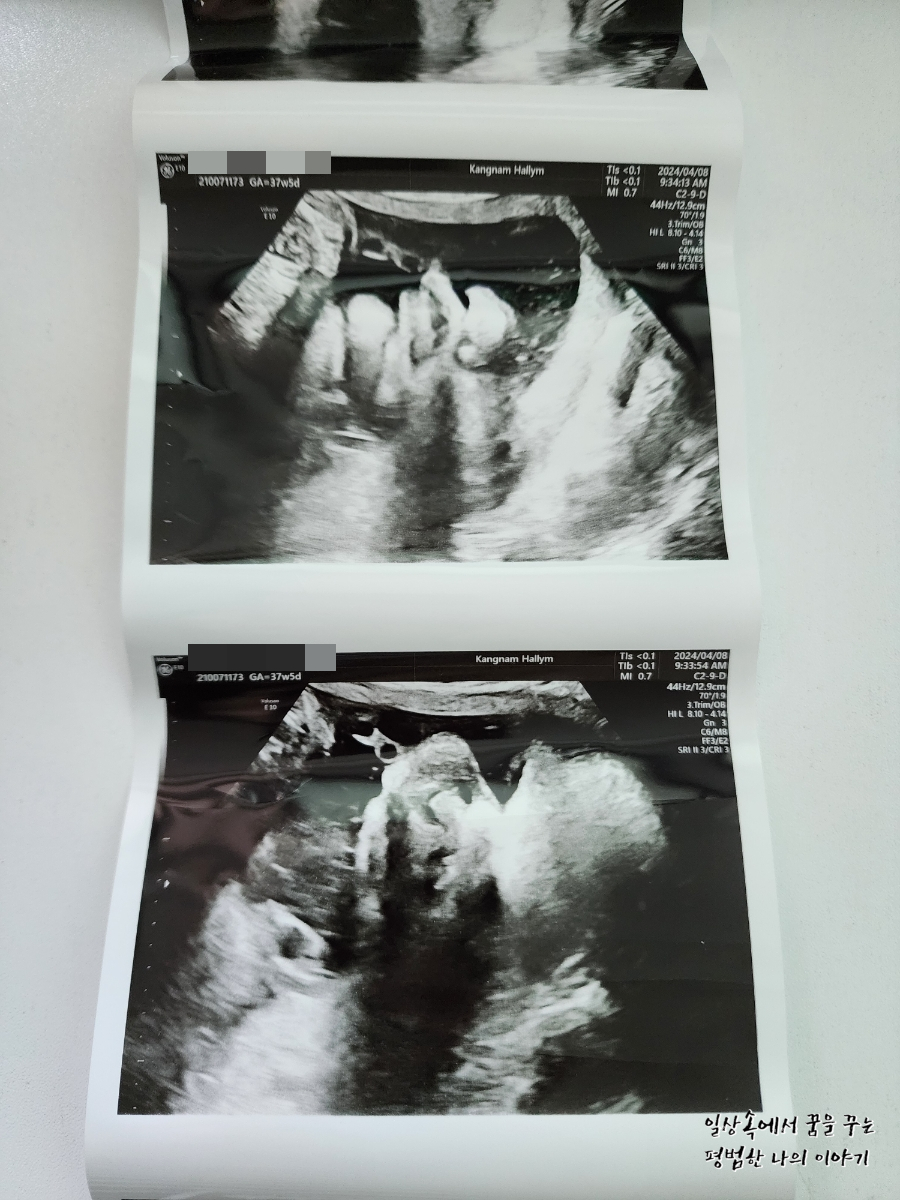

2024년 4월 8일(월요일)

BPD(Biparietal Diameter, 위에서 볼 때 태아 머리 단면의 가장 긴 길이): 9.61cm

HC(Head Circumference, 태아 머리둘레): 34.05cm

AC(Abdominal Circumference, 배 둘레): 37.65cm

FL(Femur Length, 허벅지뼈 길이): 7.22cm

GA(Gestational Age, 임신 주차): 37주 차 5일

EFW(Estimated Fatal Weight, 태아 예상 체중)=EBW(Estimated Body Weight): 4044g

FHR(Fetal Heart Rate, 심장박동 수): 157bpm

CL(Cervical Length, 자궁경부 길이): 정상

AF(Amniotic Fluid, 양수): 정상